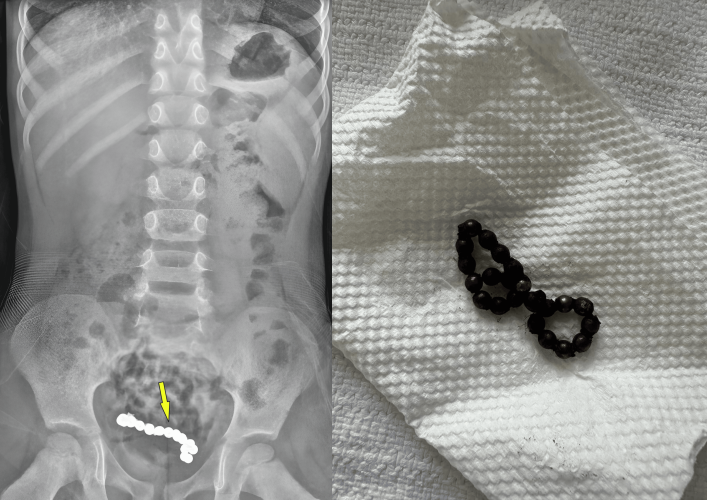

“1년동안 배 아파” 4세 남아…뱃속에 ‘자석 22개’ 들어있었다